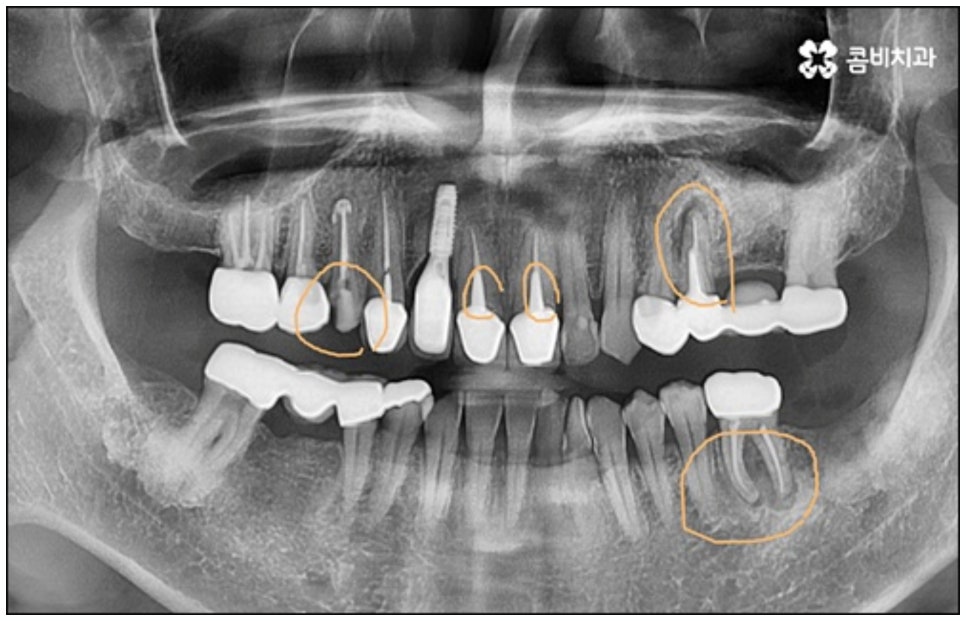

다만 누구나 당일임플란트 시술이 가능한 것은 아니기 때문에 주의가 필요한데요, 위에서 언급했던 사전 치료가 필요한 경우와 같이 바탕이 되는 잇몸 건강이 좋지 않다면 바로 식립을 진행할 수 없기 때문에 시술 전 정밀 검사를 통해 꼼꼼하게 진단을 하고 각자의 상황에 대해 담당 의료진과 충분하게 상담을 해 보시는 것이 중요하다고 할 수 있습니다.

예를 들어서 오랜 치주염으로 퇴축이 진행되어 잇몸이 이미 많이 내려앉은 경우, 심한 치아 뿌리 염증으로 잇몸뼈가 상당부분 녹은 경우, 노화나 지병으로 인해 골밀도가 낮고 잇몸뼈가 약해져 지지가 어렵거나 쉽게 부서지는 등 뼈의 상태가 양호하지 못한 경우 등에 있어서는 발치 후 즉시 임플란트를 식립하는 방식이 적합하지 않으며 치아가 한꺼번에 여러개 손상된 경우에도 6~8주 정도의 시간을 두고 무리하지 않게 단계적으로 식립하는 것이 혹시 모를 부작용을 막고 장기적인 안정성을 높이는 방법이라고 할 수 있어요.

이때 당일임플란트 시술은 정밀함을 요하는 고난도 치료에 속하는 만큼 의료진의 숙련도에 영향을 많이 받기 때문에 안정적으로 골이식재가 자리잡고 식립된 임플란트가 보다 오랜 기간 강한 저작력을 견딜 수 있도록 지속력을 높이기 위해서는 다양한 환자분들의 임상 치료 경험과 뛰어난 노하우, 정확한 판단력 및 세심한 실력을 갖춘 의료진에게 시술을 받으실 필요가 있습니다.

또한 한 번 식립된 인공 치근이 뼈조직과 골융합되고 난 다음에는 그 위치와 방향을 수정하기 어려운 만큼 혹시 모를 부작용이나 재수술 위험 없이 임플란트 치아를 사용할 수 있도록 안정성이 검증된 정품 재료를 사용하고 있는지, 잇몸 상태와 구강 구조를 세밀하게 체크할 수 있는 3D CT와 같은 정밀 검진 장비를 활용하는지 등등을 함께 꼼꼼하게 체크해 볼 필요가 있어요. 그리고 언급했던 것처럼 사후 관리 역시 임플란트 수명에 큰 영향을 주니 철저한 케어 시스템을 갖추고 임플란트 유지 관리를 도와주는 치과에서 진행하는 것 역시 중요하다고 할 수 있습니다.